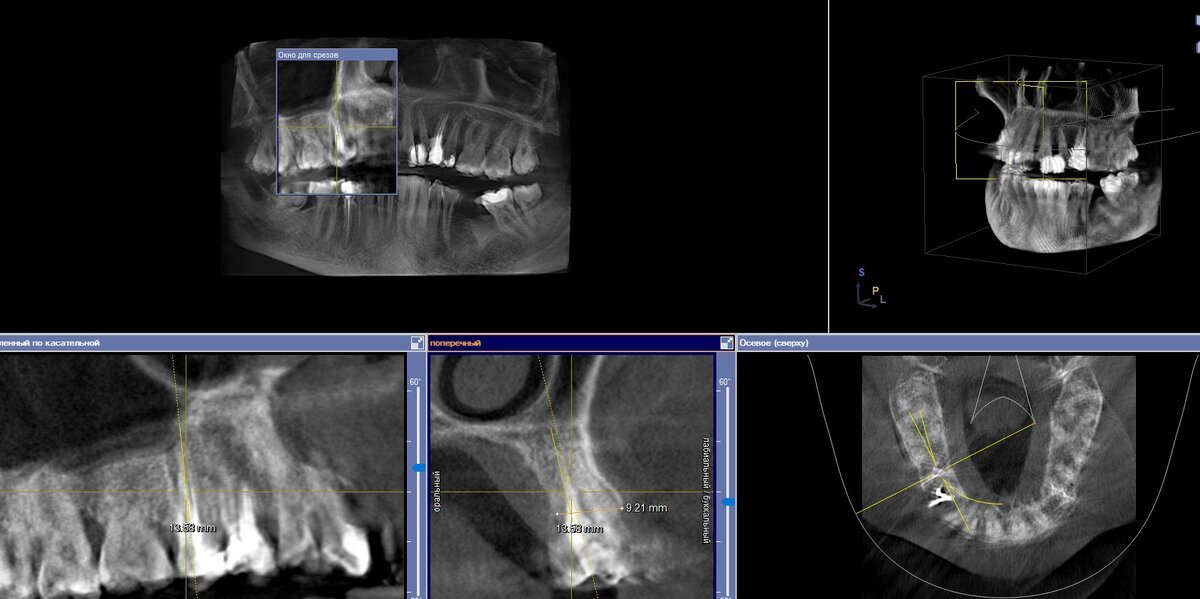

Исходная ситуация. Зуб ранее давно лечен, на снимке отсутствует какое-либо воспаление вокруг корня, есть достаточное количество костной ткани в высоту и ширину, что даёт нам заниматься одномоментной имплантацией:

Делаем контрольный снимок:

Направление имплантата и его позиция оптимальны